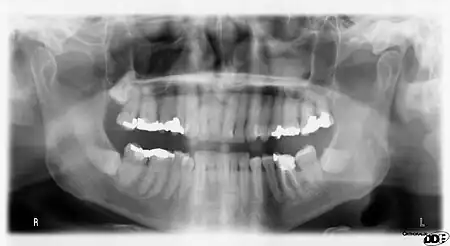

Panoramic films

Panoramic films are extraoral films, in which the film is exposed while outside the patient's mouth, and they were developed by the United States Army as a quick way to get an overall view of a soldier's oral health. Exposing eighteen films per soldier was very time consuming, and it was felt that a single panoramic film could speed up the process of examining and assessing the dental health of the soldiers; as soldiers with toothache were incapacitated from duty. It was later discovered that while panoramic films can prove very useful in detecting and localizing mandibular fractures and other pathologic entities of the mandible, they were not very good at assessing periodontal bone loss or tooth decay.[18]